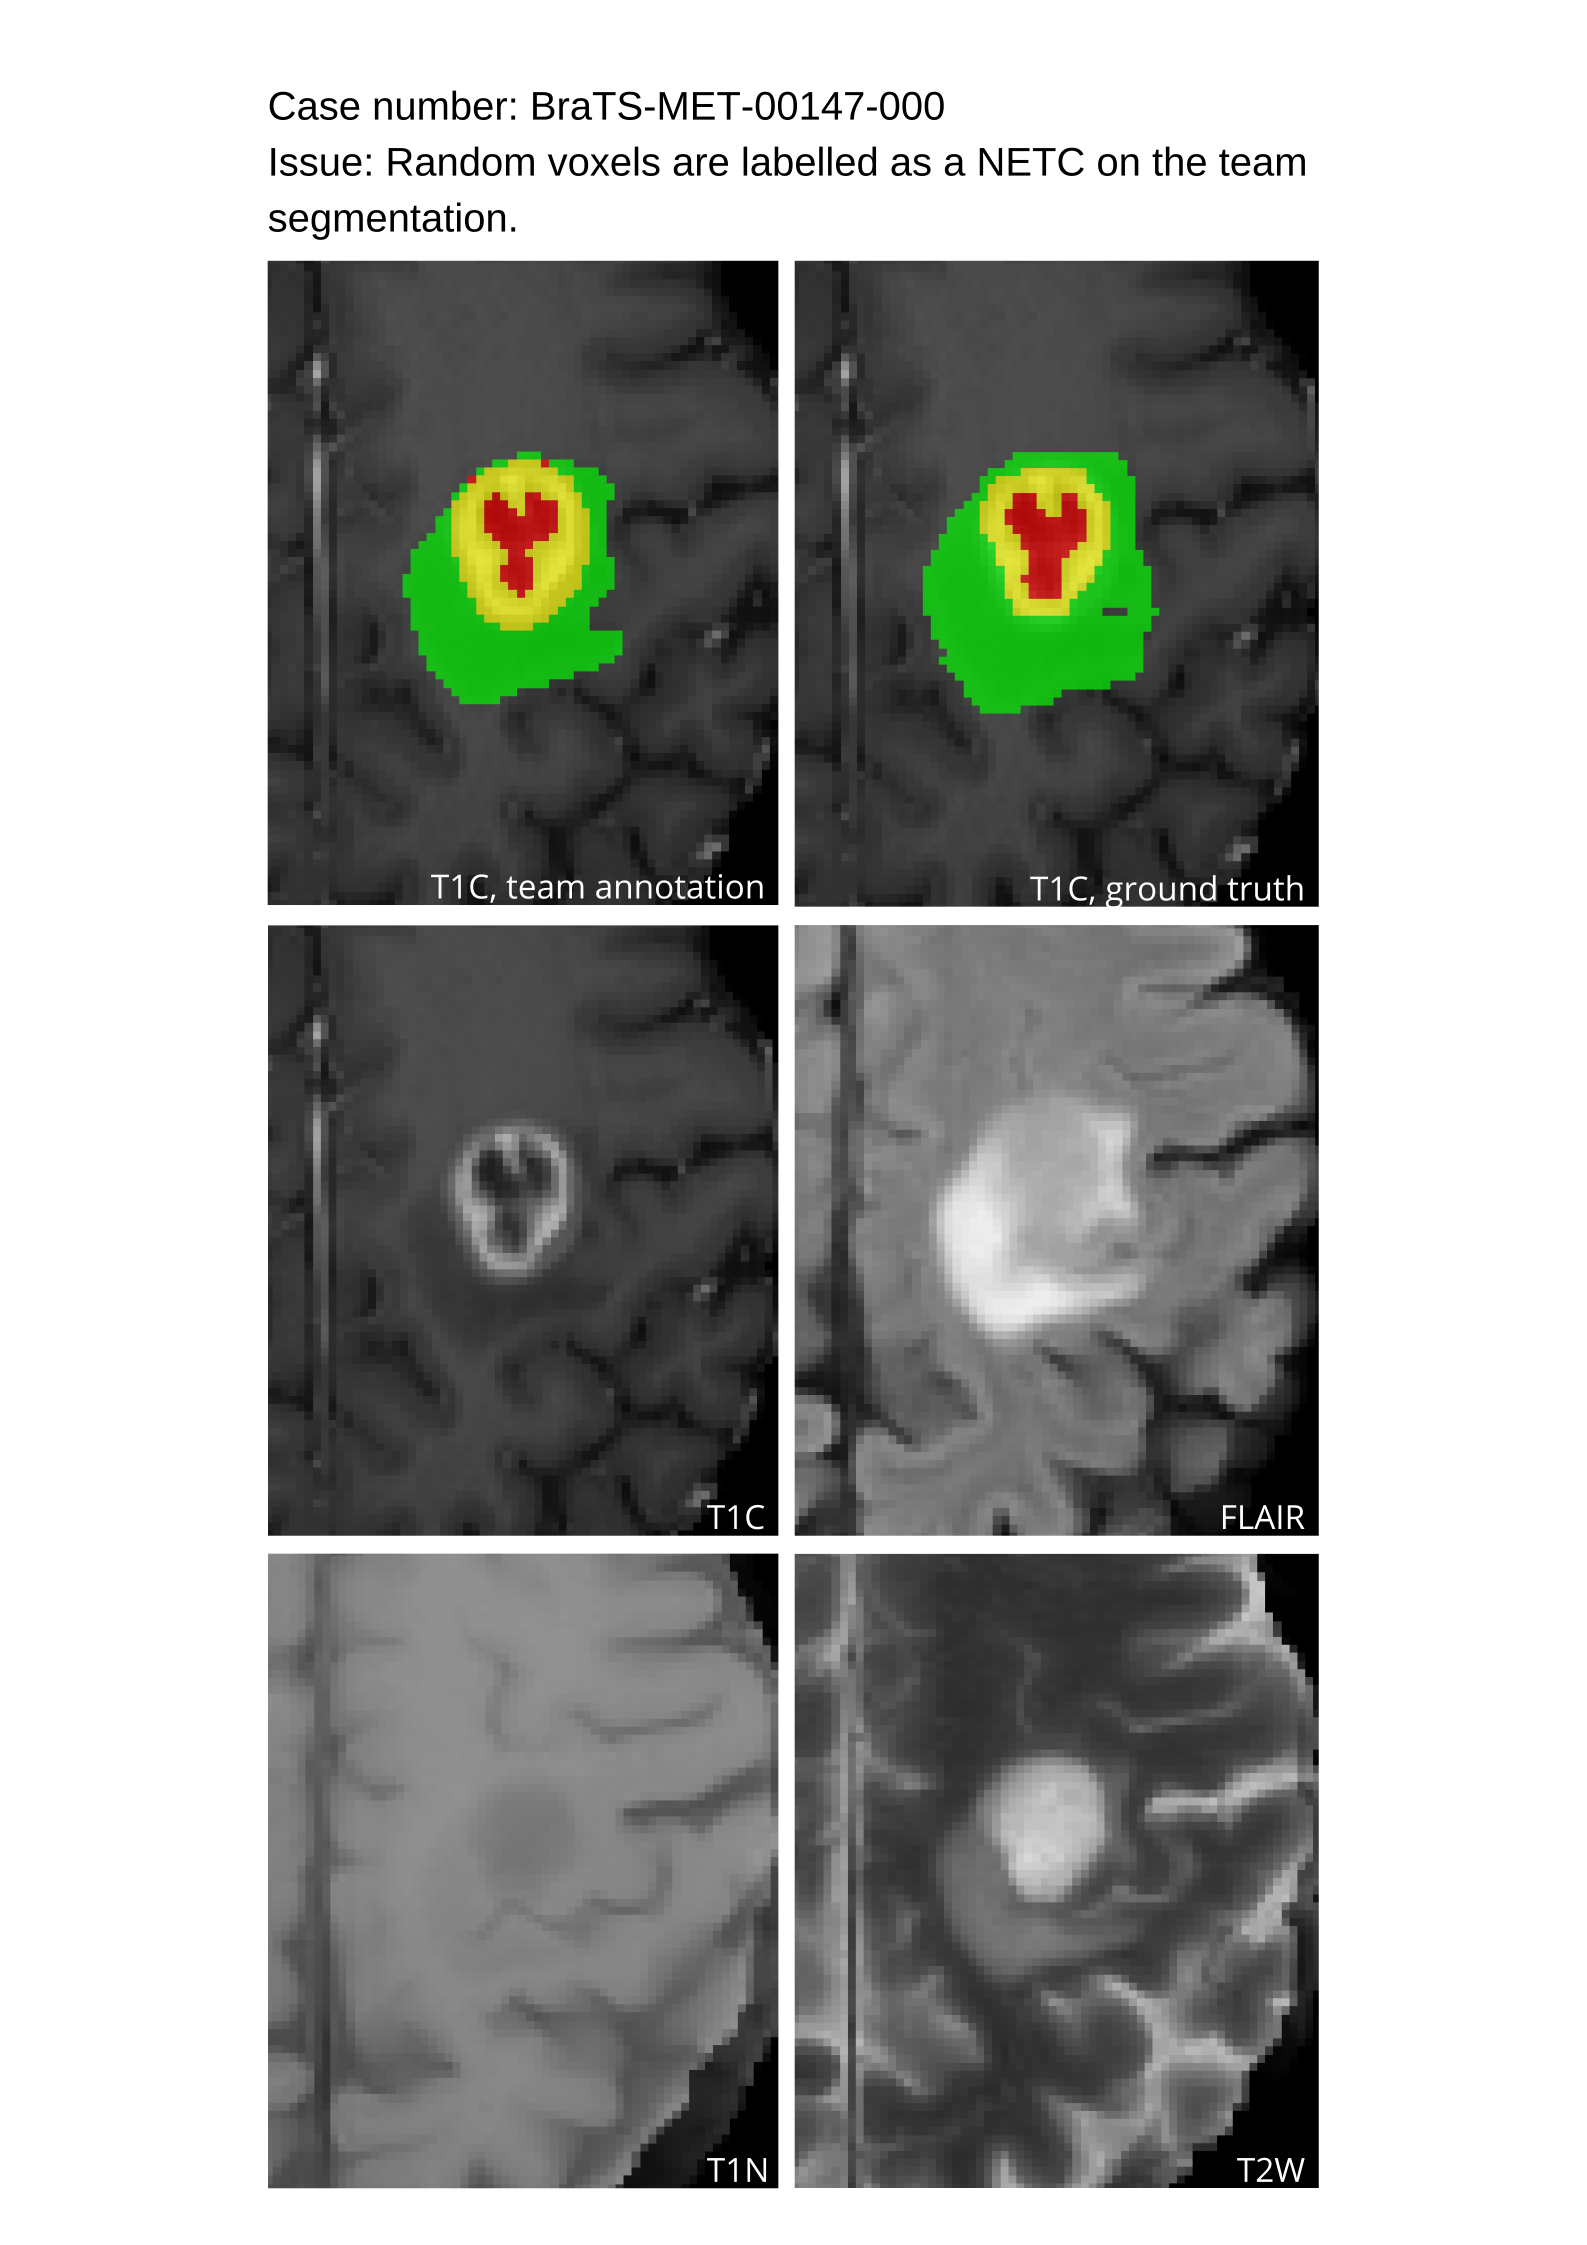

4.9 Common Errors of Automated Segmentations

Based on observations from previous BraTS challenges, common errors in automated segmentations were identified. The most typical errors in the current challenge included:

1. 1.

Automated algorithms missing small metastases. Enhancing metastasis was fused using the minority voting algorithm to aggregate all enhancing tumor voxels identified by the three algorithms. However, many small metastases were missed and were manually segmented by neuroradiology attendings.

2. 2.

Segmentation of white matter changes from microvascular disease. Peritumoral edema segmentations were checked by neuroradiology attendings and modified.

3. 3.

The segmentation of non-enhancing lesions that have intrinsic T1 hyperintensity. Voxels with intrinsic T1 hyperintensity were manually removed from ET segmentations.

These insights led to specific adjustments in the annotation process to enhance accuracy.